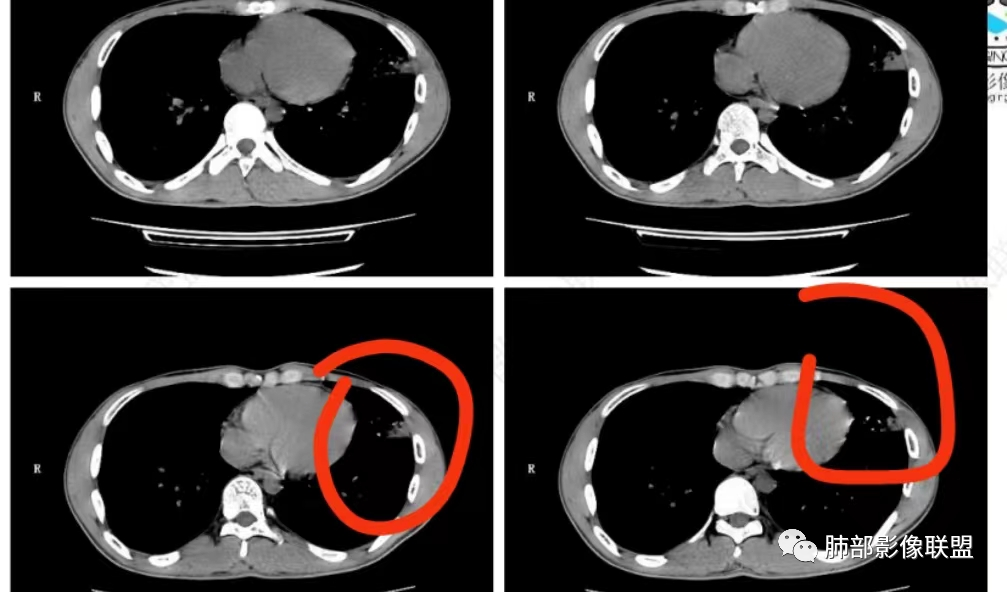

唐老师的经典名言:支扩背景的肺,判断病原体时一定要判断出支扩合并肉芽肿,或无肉芽肿性支扩。

实变边缘太模糊,渗出太明显了,不符合肉芽肿的特点

支扩背景的肺,肺里有多发实变或结块,实变无肉芽肿就要考虑诺卡?

NTM支扩外一般无渗出性病变,而铜绿支扩外渗出常见

中叶内侧段的渗出病灶内支扩,支持铜绿,不支持NTM

你们再看这两个层面!支扩背景下出现肉芽肿病变。